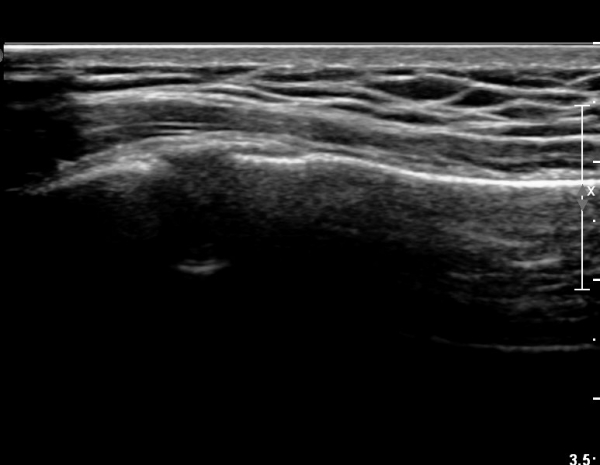

ÃÊÀ½ÆÄ °Ë»ç : ¼Õ¸ñ ¼ö±Ù°ü ±ÙÀ§ºÎ Ⱦ´Ü¸é°Ë»ç¿¡¼­ Äá¾Ë»À Ç¥ÃþÀ¸·Î ¾à°£ÀÇ ¿¬ºÎÁ¶Á÷ ºÎÁ¾ÀÌ °üÂûµÊ(»çÁø 1).

ŽÃËÀÚ¸¦ ¾à°£ ¸»´ÜÀ¸·Î À̵¿ÇÏ´Ï ¿¬ºÎÁ¶Á÷ ºÎÁ¾ÀÌ ´õ¿í ½ÉÇÏ°Ô °üÂûµÇ°í(»çÁø 2),